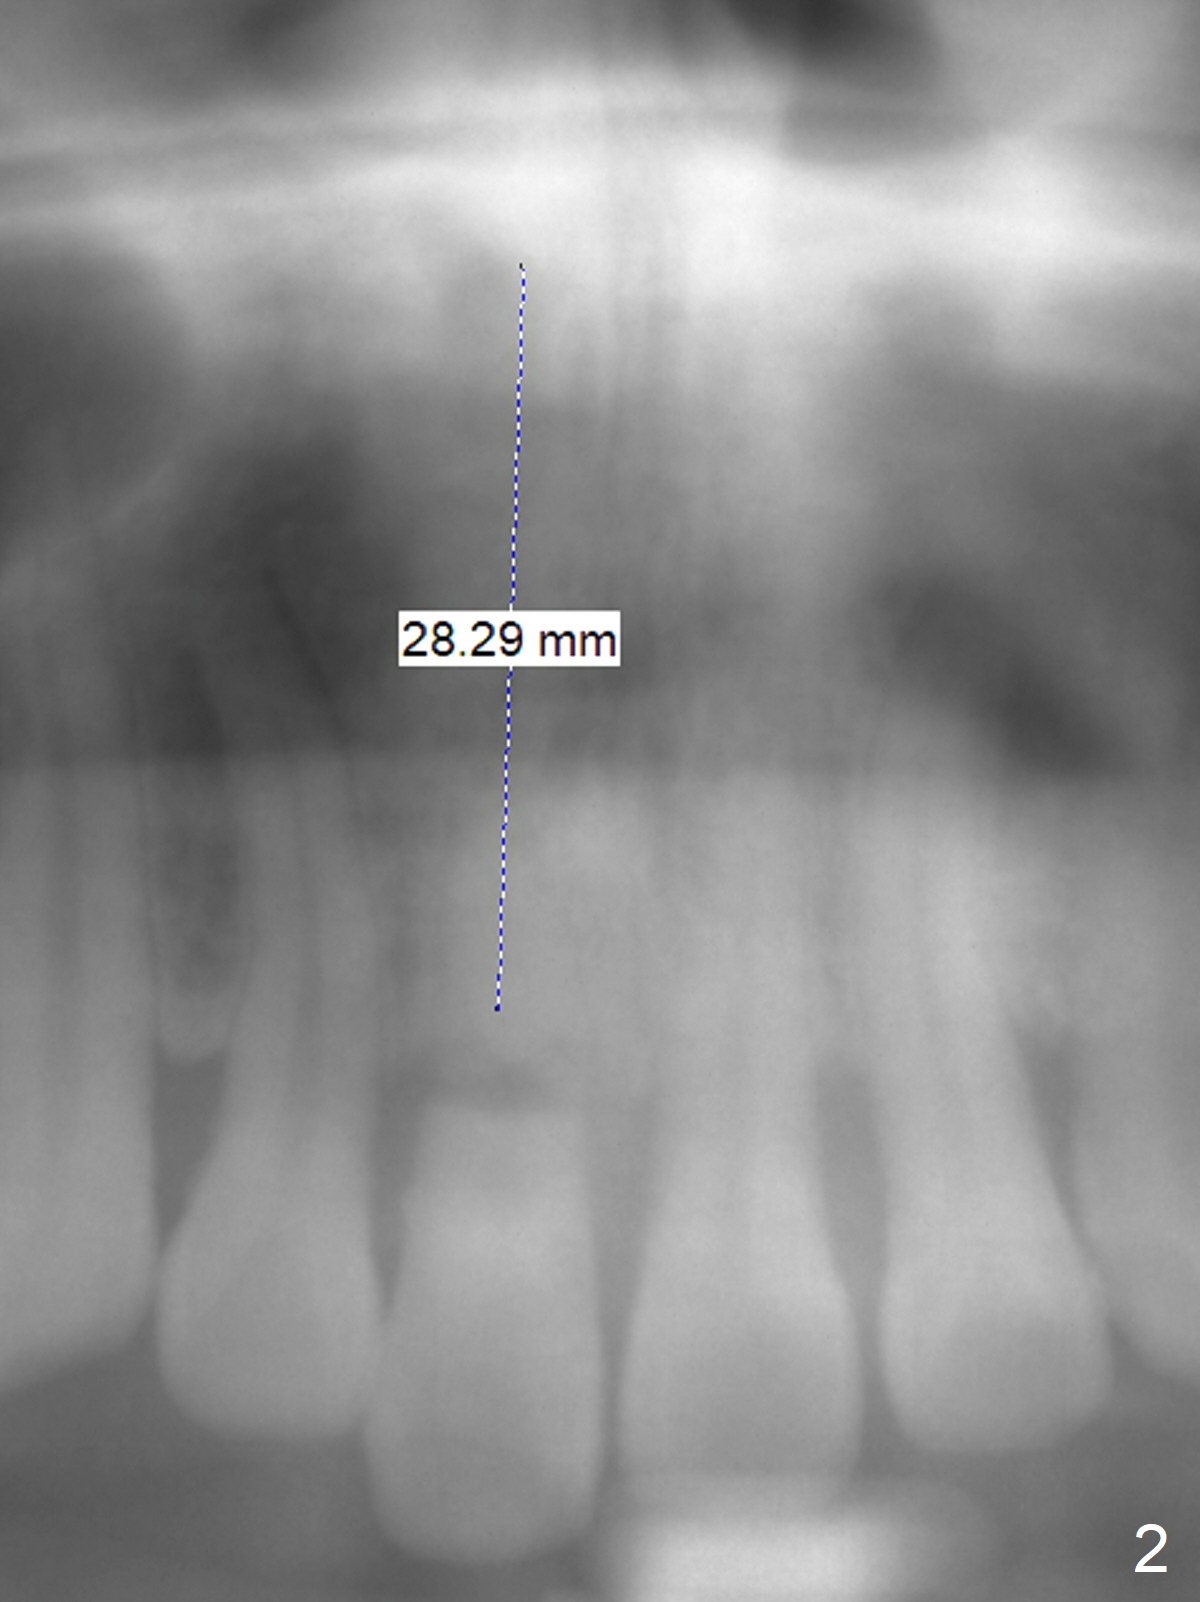

Longest Bone-Level Implant

A 37-year-old man has fractured the root of the tooth #8 for a year (Fig.1). It appears that the longest bone-level implant is indicated (Fig.2). Take preop photos and PA if it is symptomatic with fistula.